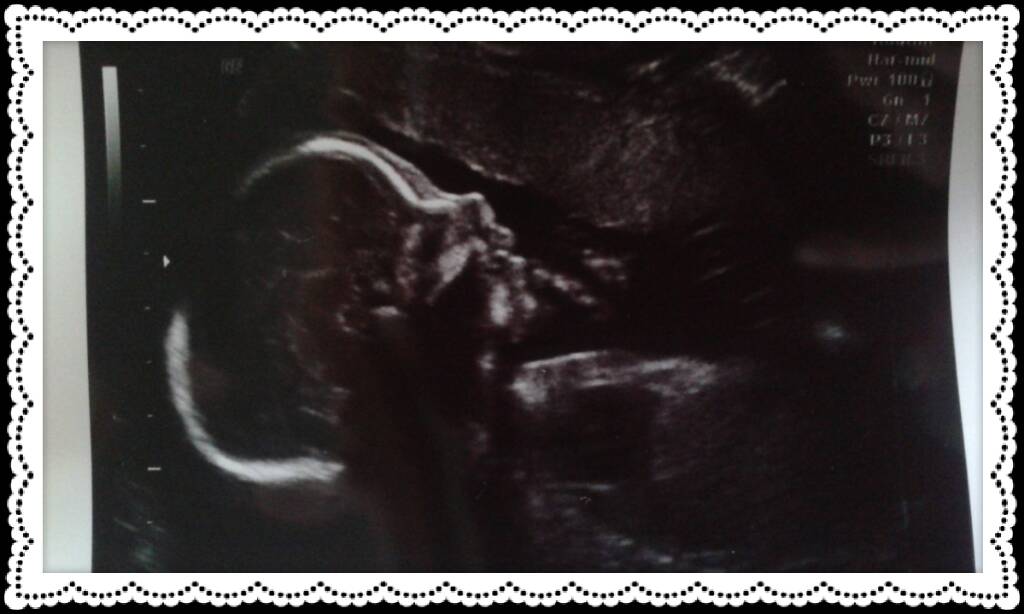

Omaa napaa lyhkäisyydesdään: Täällä käytiin rakenneultrassa ja kaikki hyvin. Vastas viikkoja joita nyt kertynyt jo 21+4 ja painoa hällä oli 393g ♡ potkuja olen tuntenut jo viitisen viikkoa ja nyt ne näkyy jo päällepäinkin. :) masuakin on jo reippaasti ettei voi erehtyä.. :D

Liitteet

• 1430736016718.jpg

1430736016718.jpg

62.1 KB · Katsottu: 169

Ihania ultrakuulumisia j3nnillä :Heartred

Oi j3nni mikä ihana ultrakuva!